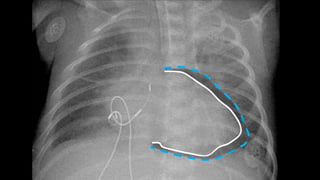

PNEUMOPERICÁRDIO

Sinal do diafragma contínuo